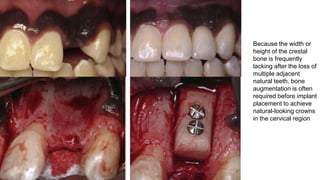

Because the width or

height of the crestal

bone is frequently

lacking after the loss of

multiple adjacent

natural teeth, bone

augmentation is often

required before implant

placement to achieve

natural-looking crowns

in the cervical region